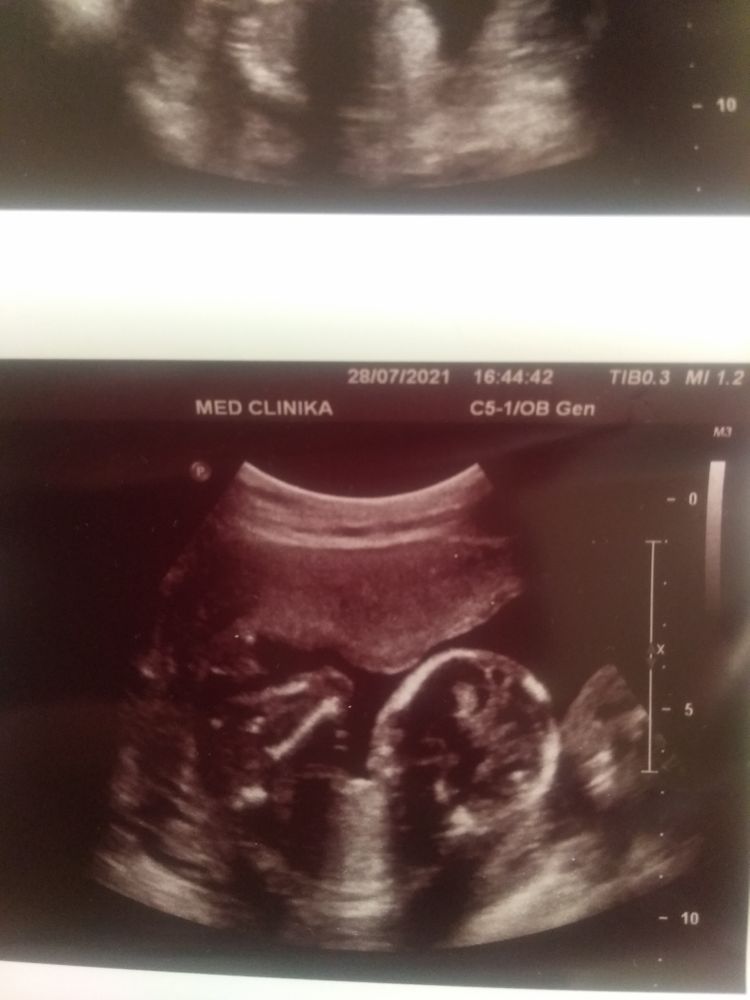

Сегодня была на узи.Срок по мд 16.0.По узи 17.2. Опережаем срок.Ну подскажите,это фото с полом?Узистка сказала мальчик будет.Вес 180гр.Третий сосуд в пуповине увидели и даже показали.Я очень рада.Зато в головке нашли какие то кисты.Узистка сказала ничего страшного,дальше котроль в 20 недель.Очень надеялась на девочку)Может еще не точно определила?! Кто знающий,помогите.

Ну если я ниче не путаю, то на первом фото очень отчетливо виден мальчик без вариантов 🤷♀️

КАРАМЕЛЬКА, ну а у основания что там такое широкое может быть? Похоже на мошонку вид снизу🤔 а потом пенис идёт.